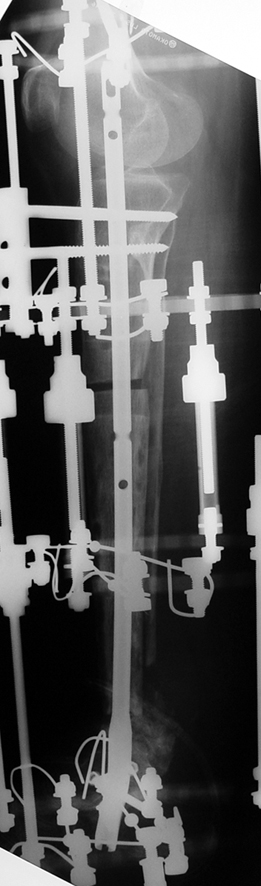

Kaynamayan kemik uçlarının çıkartılması, damarlı fibula veya fibula grefti, damarlı kas greftleri ile birlikte internal fiksasyon uygulamaları, elektrik stimulasyon gibi uygulamalar kaynamamada bir şeçenektir. Fakat kısalık ve deformite gibi ek patolojiler tedavisinde kısıtlı kalmaktadır. İlizarov eksternal fiksatörü ile uygulanan distraksiyon osteogenezi uygulamaları ile birlikte yapılan psödoartroz sahasından akut kısatma ve aynı kemikteki diğer segmentten uzatma yapılmaktadır.

Ilizarov ve arkadasları, kendi geliştirdikleri yöntem ve fiksatörle, aynı anda, hastanın günlük aktivitelerini kısıtlamadan, eklem fonksiyonlarını koruyarak kaynamayı basarmıs,deformiteyi düzeltmis, uzunlugu yeniden sağlamıstır. Bu teknik sayesinde kemik defektlerinin kapatılması ve enfeksiyon gibi hastaya morbidite getiren ek patolojiler giderilmiş aynı zamanda kısalıkta telafi edilmiştir.

Vaka 1